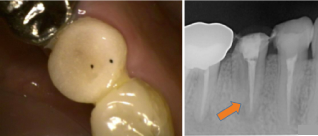

下の奥歯の違和感よ腫脹を主訴に来院。下顎大臼歯の根管内の感染物質を除去した後、徹底的に洗浄消毒を行い、炎症症状の消失となった。

左下小臼歯の動揺を主訴に来院。根管内容物と最近感染組織を除去し、根管内を消毒し吸収した骨が回復となった。

歯根周囲に骨透過像が認められる。細菌感染により骨が吸収が疑われる。骨吸収により動揺が認められた。

歯根周囲に骨透過像が認められる。細菌感染により骨が吸収が疑われる。骨吸収により動揺が認められた。

根管治療後。歯根周囲に骨の回復を認める。歯の動揺も無くなり、被せ物をして、問題無く機能している。

根管治療後。歯根周囲に骨の回復を認める。歯の動揺も無くなり、被せ物をして、問題無く機能している。